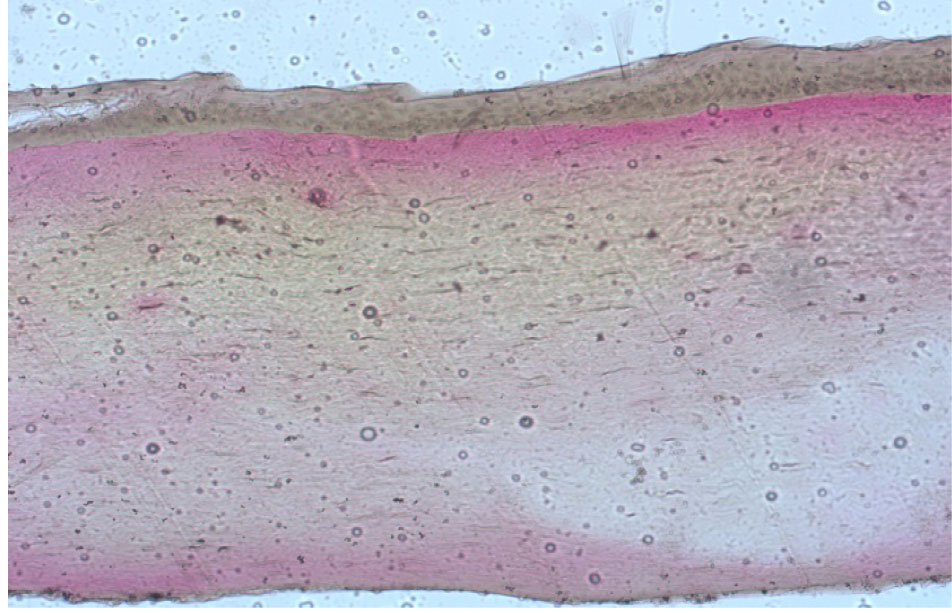

Во второй группе, где проводилась ограниченная по диаметру эксимерлазерная деэпителизация на глубину ⅔ эпителиального слоя с последующим механическим удалением оставшейся ⅓ эпителия, визуализировались как деэпителизированные участки, так и зоны с сохраненным эпителием, где определялась слоистость его строения от рядов кубических до плоских клеток без элементов ороговения (рис. 6). При окраске по Ван Гизону видно, что такие участки деэпителизации дали возможность пройти раствору рибофлавина в строму роговицы на всю ее глубину, что отразилось в появлении лакунарных пространств на всей площади поперечного среза роговицы до десцеметовой мембраны. Коллагеновые волокна при этом сохранили однонаправленность ориентации параллельно поверхности роговицы.

Рис. 6. Роговица свиного кадаверного глаза после проведения частичной эксимерлазерной деэпителизации, окраска по Ван Гизону, об. ×10

Наибольшее разрыхление передней стромы роговицы отмечалось в проекции зоны деэпителизации. Однако аналогичная картина с появлением большого количества лакунарных пространств между волокнами коллагена наблюдалась и под сохраненным эпителием, что говорит о наличии межламеллярного распространения раствора рибофлавина на область, превышающую по размерам зону деэпителизации, что подтверждает целесообразность проведения деэпителизации только в зоне кератоконуса и осуществления ультафиолетового облучения как в зоне полной деэпителизации, так и перифокально с захватом роговицы с сохранным эпителием.